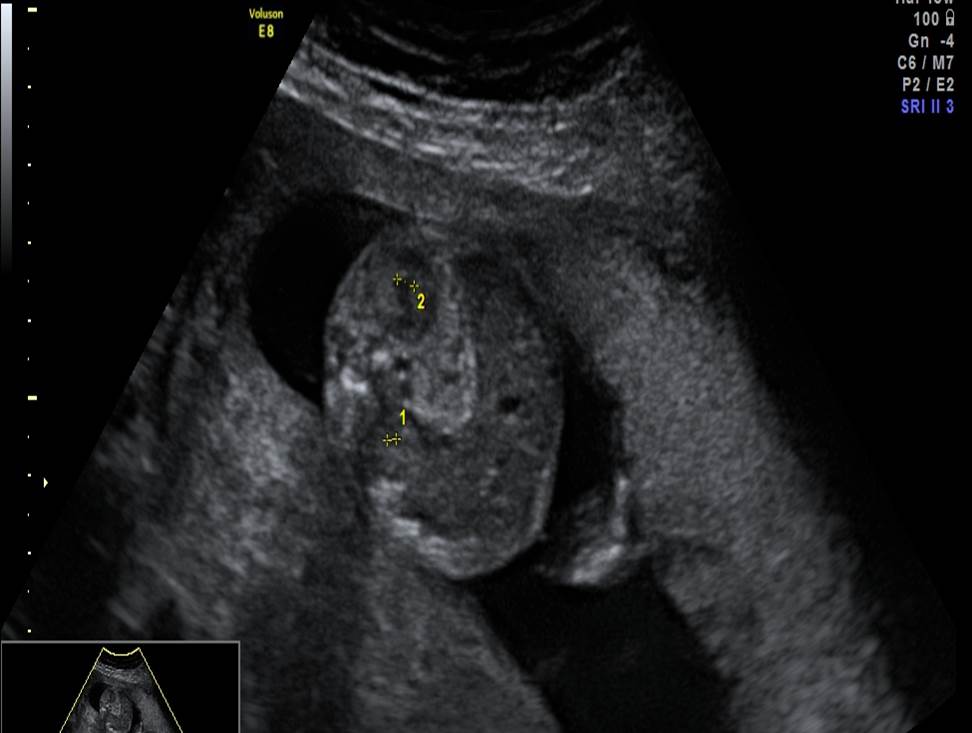

- Проанализируйте изображения плода в 22 недели, есть ли у него какие-либо маркеры хромосомной патологии?

- Необходимо ли рекомендовать инвазивную диагностику? Пациентке 30 лет, в 1 триместре комбинированный риск по трисомии 21 — 1:1200